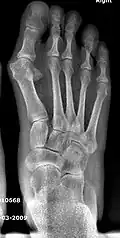

![]() Fig. 8a. Painful hallux valgus and metatarsus primus varus deformity recurrence of left foot after osteotomy surgery | |

- For severe bunion deformity correction (Fig. 7)

- For recurrence correction after osteotomy procedure (Fig. 8)

Late deformity recurrence can happen after osteotomy (bone-breaking) procedures because osteotomy surgeries do not specifically stabilize first metatarsal bone.